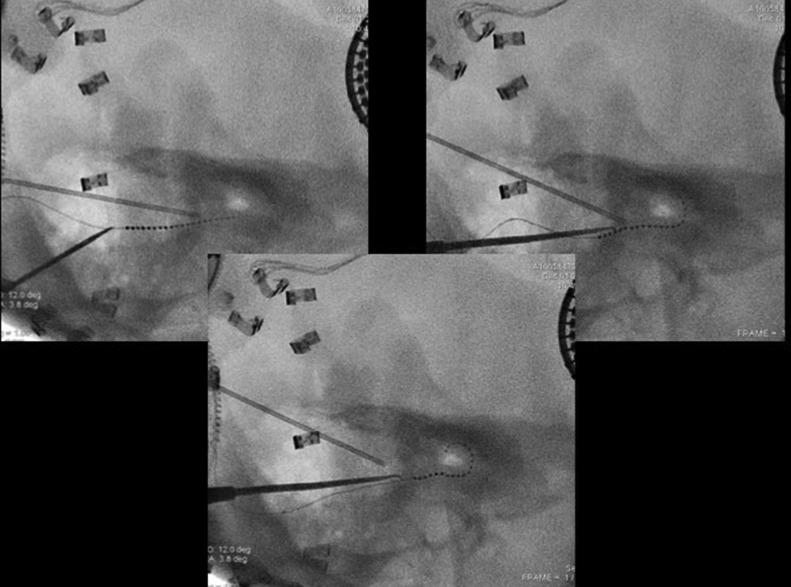

The cochlear implant is an implanted auditory prosthesis that can restore severe and profound hearing loss. About 20% of patients with congenital sensorineural hearing loss have a malformation of the inner ear. These abnormalities must be investigated before a cochlear implant because they can lead to intra and postoperative complications and/or anomalies. Most labyrinthine malformations are well known; some are less frequent and can be underdiagnosed at the preoperative computed tomography. This report presents the case of bilateral cochlear-facial dehiscence, bony dehiscence between the facial nerve labyrinthine segment, and cochlear basal turn. In our 56-year-old patient, this malformation was misdiagnosed before the cochlear implant and revealed afterward because of abnormal facial nerve stimulation during intraoperative electrophysiological checking.

人工耳蜗是一种可植入的听觉假体,能够恢复重度和极重度听力损失。约20%的先天性感音神经性听力损失患者存在内耳畸形。在植入人工耳蜗之前必须对这些异常情况进行检查,因为它们可能导致术中及术后并发症和/或异常。大多数内耳畸形是众所周知的;有些则较少见,在术前计算机断层扫描时可能漏诊。本报告介绍了一例双侧耳蜗-面神经裂缺的病例,即面神经迷路段与耳蜗底转之间的骨质裂缺。在我们这位56岁的患者中,这种畸形在人工耳蜗植入前被误诊,后来由于术中电生理检查时面神经刺激异常而被发现。